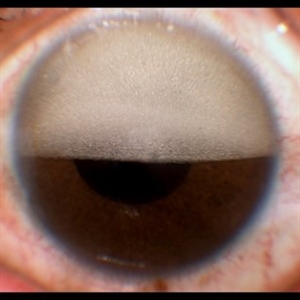

dislocated crystalline lens

Male patient 54-years-old. In the preoperative follow-up of cataract surgery, he suffered blunt trauma to the right eye, with a total dislocation of the lens.

Photographer: JEFFERSON R SOUSA - Study Center and Ophthalmological Research Dr. Andre M V Gomes, Institute Dr. Suel Abujamra São Paulo-Brazil

Imaging device: Topcon TRC-50 DX, Imaginet 5.0, angle de 50 graus. Flash 18W-S

Condition/keywords: dislocated crystalline lens